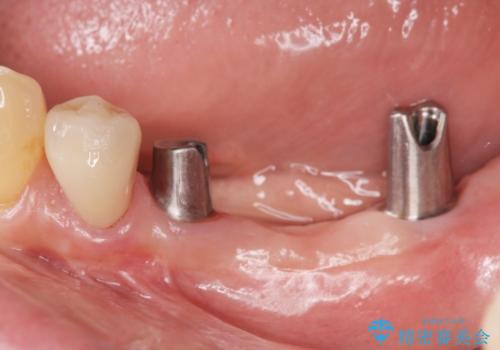

- 長年使っていた入れ歯をなくしてしまい、これを機にインプラントにしようと思い立ち来院されました。

通常長年インプラントを使用すると骨が吸収しインプラント治療が難しくなることもありますが、十分な骨が残っていたためすぐにインプラントの埋入計画を立てることができました。

長年使用してきた取り外しの必要な入れ歯と違い、しっかりと噛むことができ取り外しの必要のないインプラント治療で食事をより楽しめるようになりました。